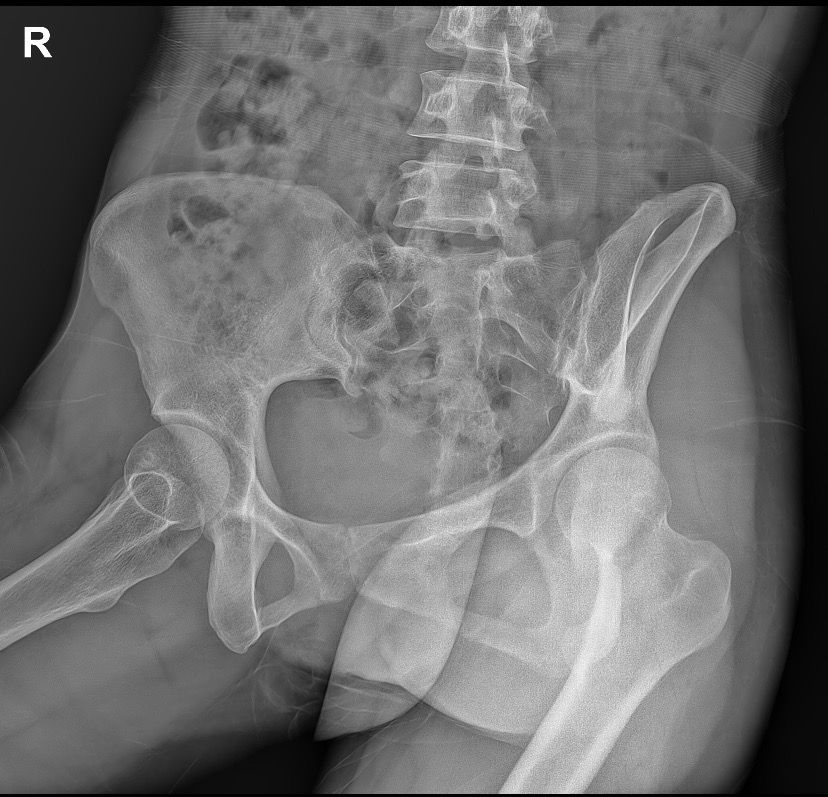

골반 x-Ray 사진 판독 좀 부탁드려요ㅜㅜ

엑스레이 찍자고 하셔서 찍었는데 왼쪽 골반뼈에 뭐가 보인다고 하시더라구요 혹인가… 하시면서 크게 신경 안쓰시는거처럼 말씀하셔서 그런가보다 하고 일단 물리치료 받고 오긴 했는데 시간이 갈수록 조금 걱정이 돼서요…

• 4번 째 사진

우선 현재로썬 위치상 자궁의 위치로 보여지지만 사진으론 정확히 위치를 파악 할 수 없습니다.

지금은 골반의 통증을 먼저 우선적으로 치료를 받으면서 경과를 지켜보시고 혹으로 의심되는 부분은 CT 또는 MRI 촬영을 권유드립니다.

다만 먼저 산부인과에 내원하셔서 엑스레이 사진을 보여주시고 자궁 초음파 또는 다른 검사를 해보시는것도 고려해보시길 바랍니다.